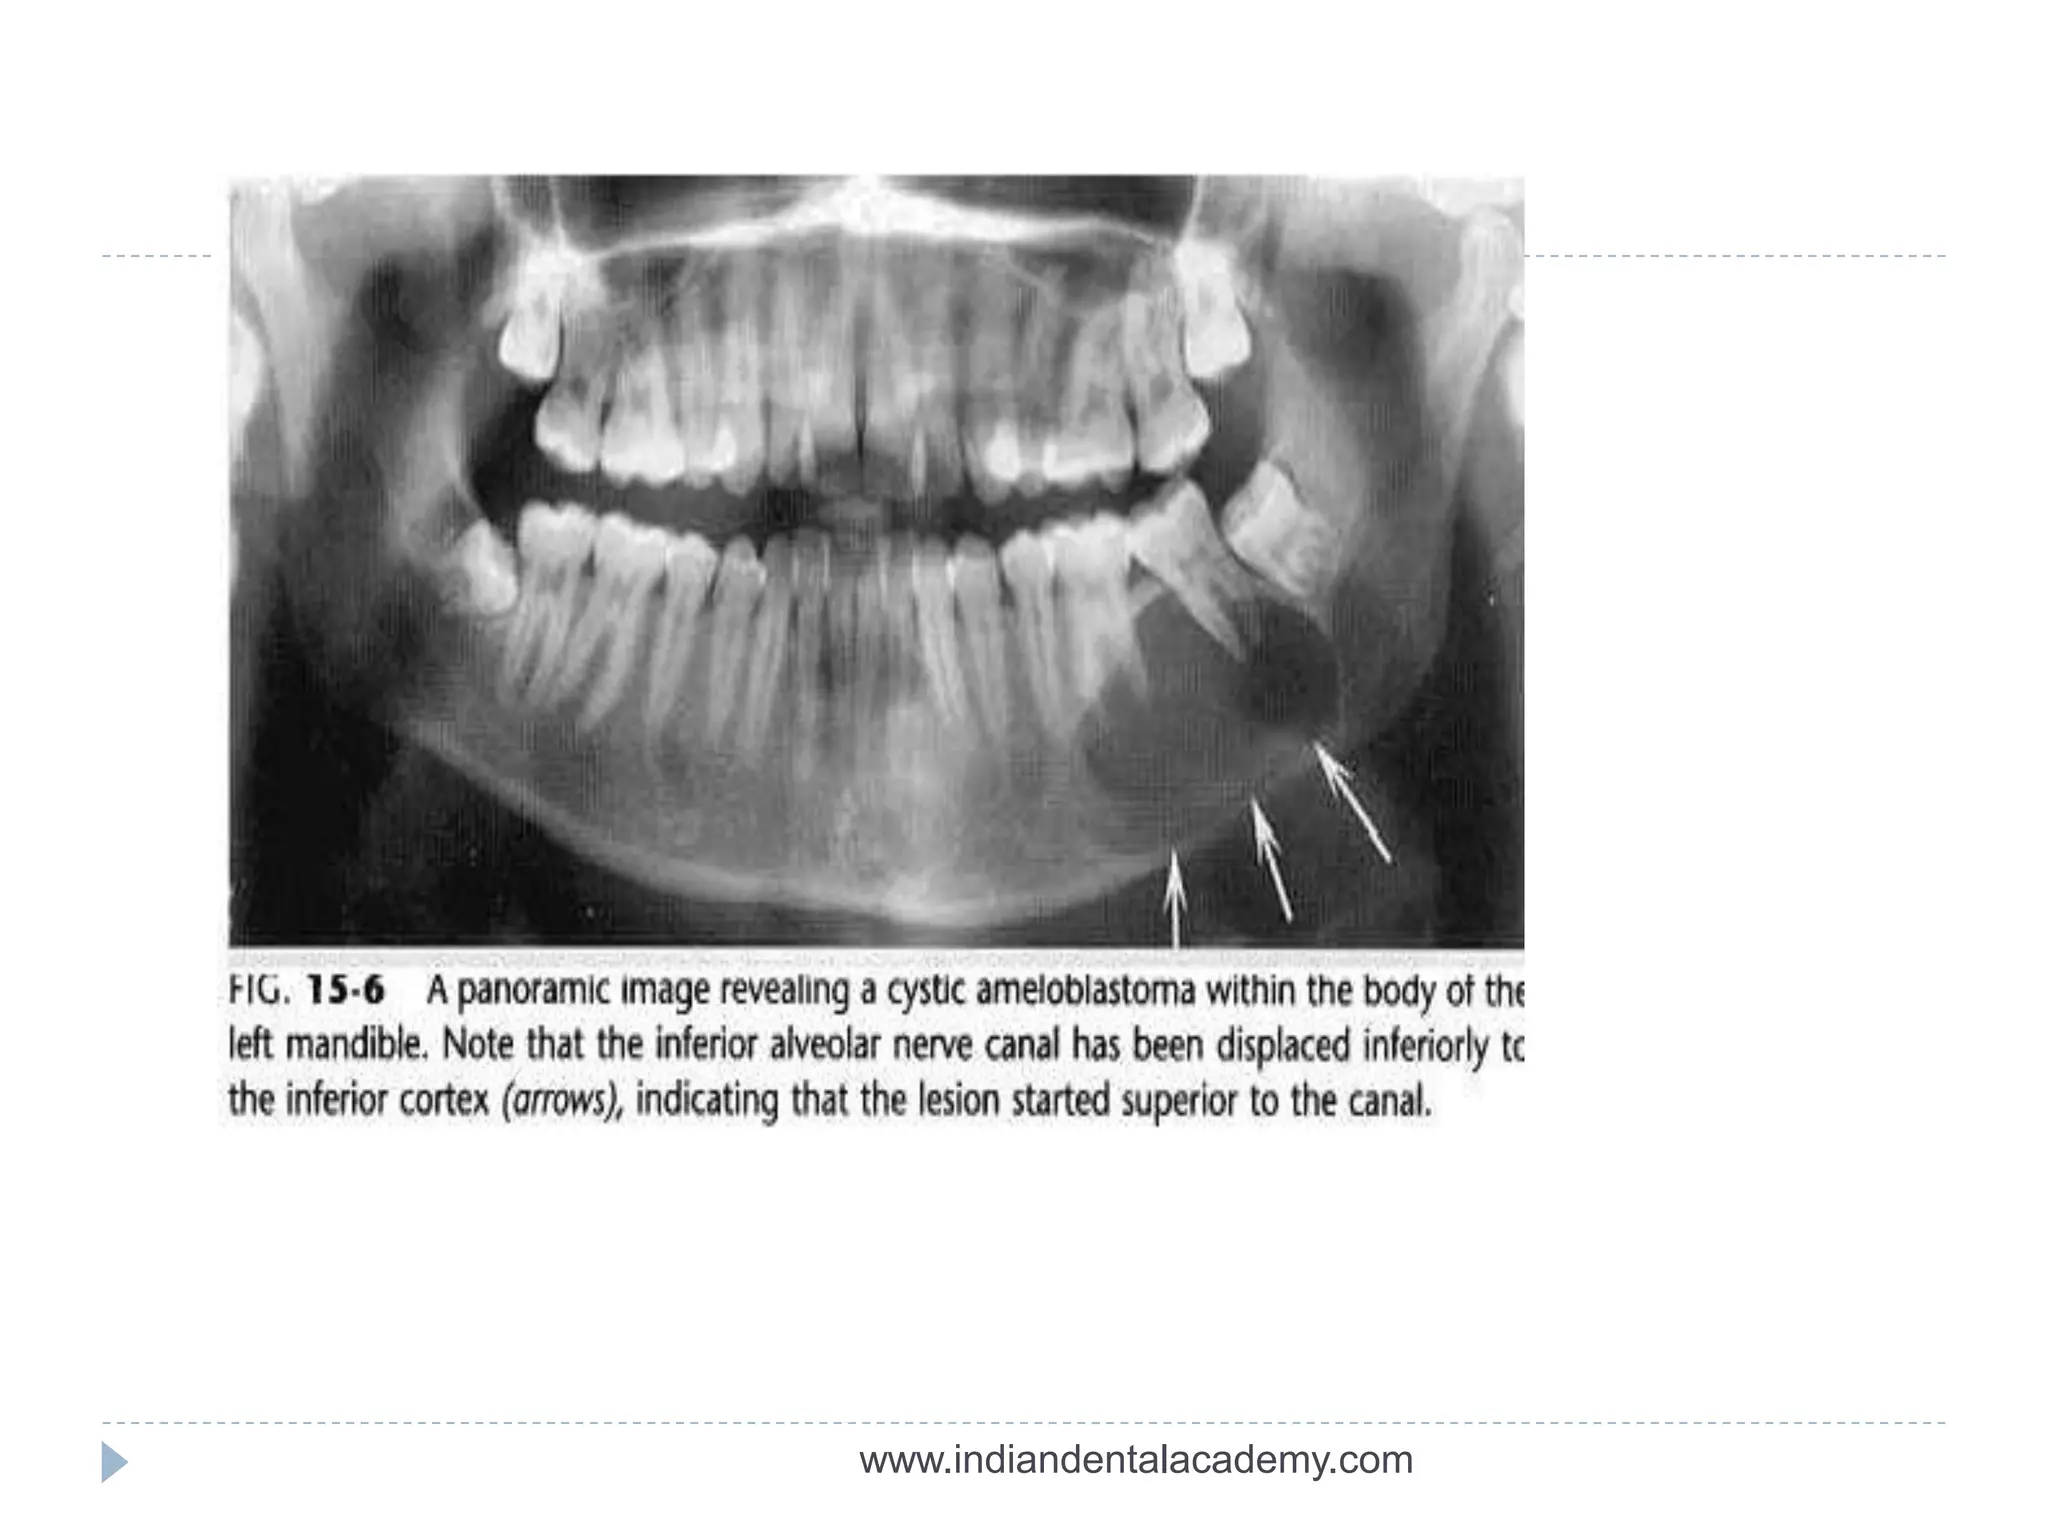

 Epicenter of the lesion is above the mandibular

canal-odontogenic in origin

 Epicenter -below IAC-non odontogenic (likely)